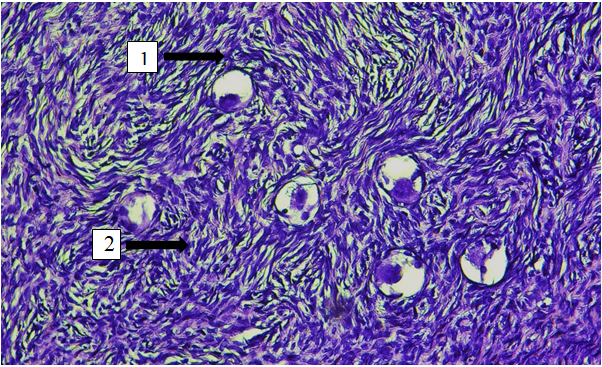

Histological FindingsA total of 110 ovaries were analyzed. Histological assessment focused on the tunica albuginea, cortex, medulla, and the density of primordial follicles.Across all age groups, ovaries exhibited a characteristic tuberous external surface, reflecting repeated ovulatory cycles. Microscopy consistently demonstrated a distinct separation between the tunica albuginea, cortical zone, and medullary zone.Age-related changes were evident in all compartments. Both cortex and medulla thickness decreased progressively with advancing age, paralleled by a marked reduction in primordial follicle density per mm² (Figure 1). These alterations were most pronounced in postmenopausal women, reflecting regression of functional ovarian tissue. | Figure 1. Structure of the ovarian cortex in a woman of reproductive age (42 years old) from the control group. 1 - primordial follicles; 2 - ovarian tissue stroma. Hematoxylin and eosin staining. 10 x 40 magnification |